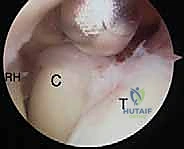

- استكشاف المفصل وإزالة الأجسام الحرة: يتم إدخال الكاميرا وضخ سائل معقم لتوسيع المفصل. يتم البحث عن أي شظايا عظمية أو غضروفية سائبة وإزالتها.

- تحرير المحفظة الأمامية (Anterior Capsulectomy): باستخدام أدوات دقيقة (Shaver & Radiofrequency)، يتم قطع وإزالة الجزء الأمامي من المحفظة المفصلية المتليفة التي تمنع المرفق من المد (Extension).

- استئصال النتوءات العظمية (Osteophyte Resection): يتم استخدام مثقاب دقيق (Burr) لبرد وإزالة الزوائد العظمية في الحفرة الإكليلية (Coronoid Fossa) والحفرة الزجية (Olecranon Fossa) لفتح المجال لحركة العظام.

- تحرير المحفظة الخلفية (Posterior Capsulectomy): ينتقل الجراح إلى الجزء الخلفي من المفصل لإزالة التليفات التي تمنع الثني (Flexion).